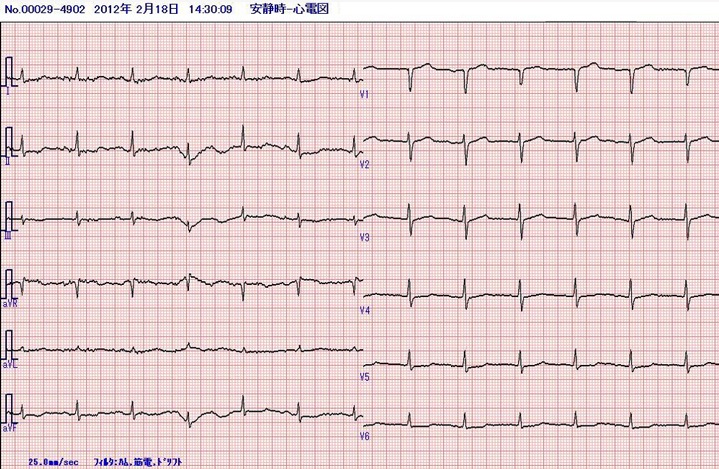

入院時の心電図

入院時の心電図は全体にlow voltageである。これは左胸腔全体に貯留した胸水の影響である(図1)。

軽度の非特異的なSTT変化を認める。この入院時の心電図と比較すると急性の病変は明らかである。